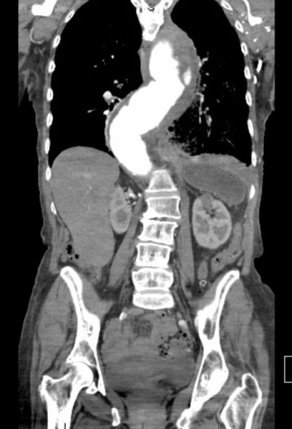

The patient’schest X-ray revealed a prominent mediastinum and opacification in the left middle and lower lung fields. The CT showed an aortic aneurysm extending from the thorax to the abdomen with rupture near T7 (blue arrow). It also showed periaortic hemorrhage with active extravasation (green arrow) likely secondary to a penetrating ulcer and bilateral pulmonary opacities concerning for hemothorax (pink arrow).